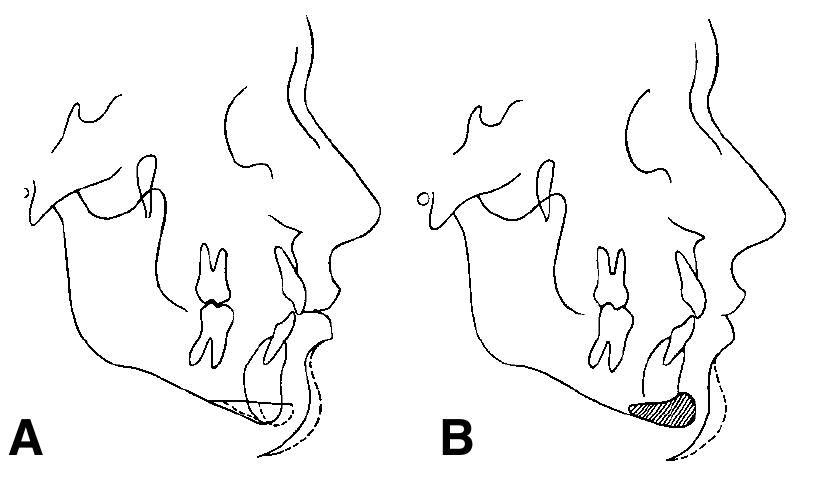

Limited oral access presents a unique challenge to prosthodontic treatment. An edentulous patient who developed microstomia after a maxillary lip resection is presented. The clinical procedure and the rationale for the treatment approach... more